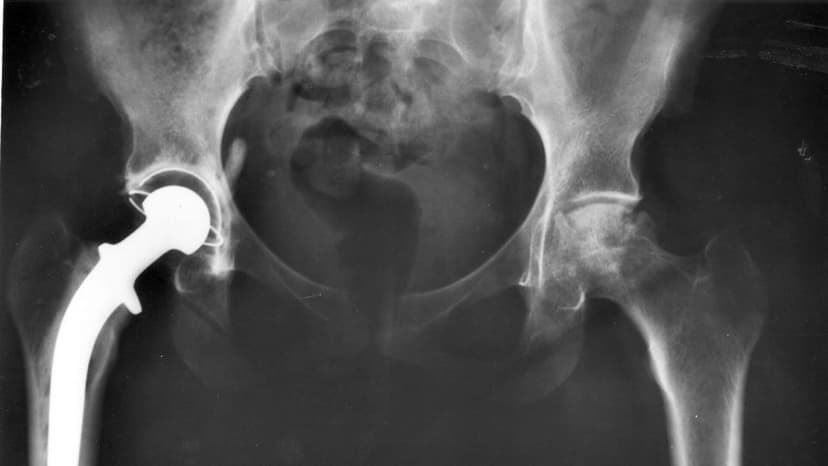

A new study indicates that hip replacement prosthetics, utilizing a combination of titanium, ceramic, and plastic, now have an extended lifespan of up to 25 years due to advancements in materials.